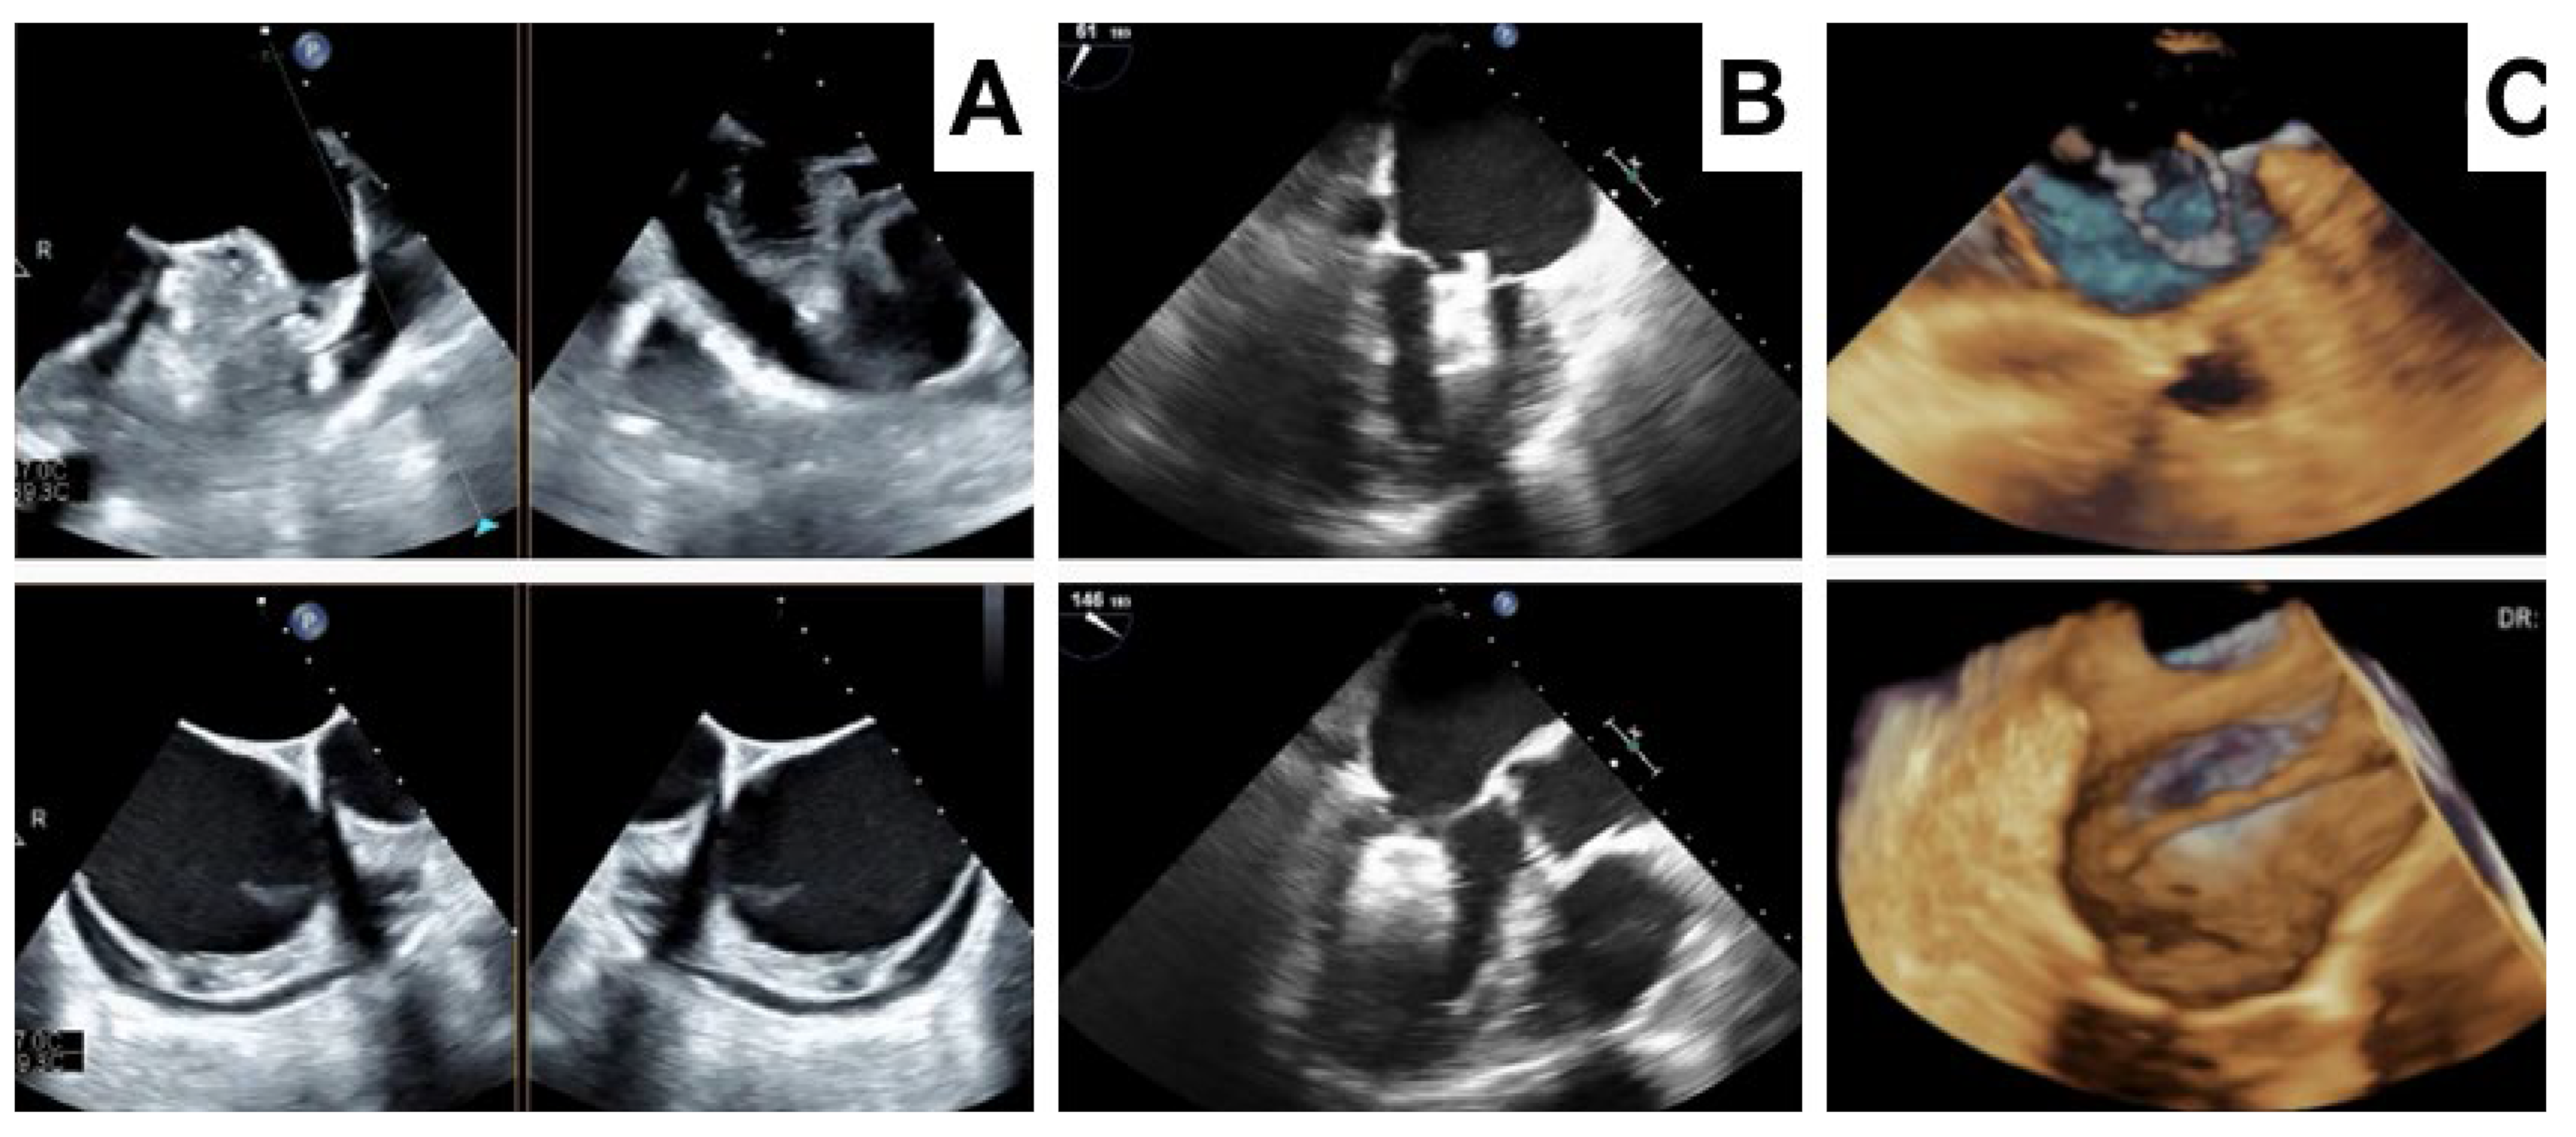

- Clemente, A.; Avogliero, F.; Berti, S.; Paradossi, U.; Jamagidze, G.; Rezzaghi, M.; Della Latta, D.; Chiappino, D. Multimodality imaging in preoperative assessment of left atrial appendage transcatheter occlusion with the Amplatzer Cardiac Plug. Eur. Heart J. Cardiovasc. Imaging 2015, 16, 1276–1287. [Google Scholar] [CrossRef]